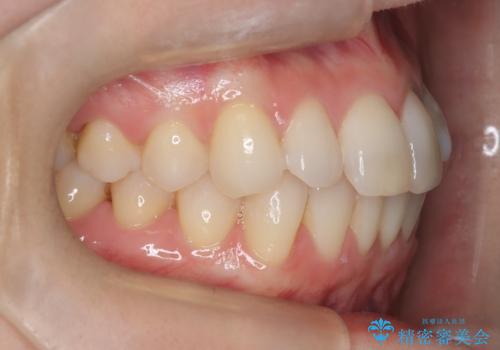

矯正後の後戻りで前歯にガタツキができてしまった インビザラインで改善

- 子どものときにワイヤー矯正をしていたが、後戻りによって前歯のガタツキが気になってきたとのことで来院されました。

アライナー矯正希望だったため、インビザラインによる治療を行いました。